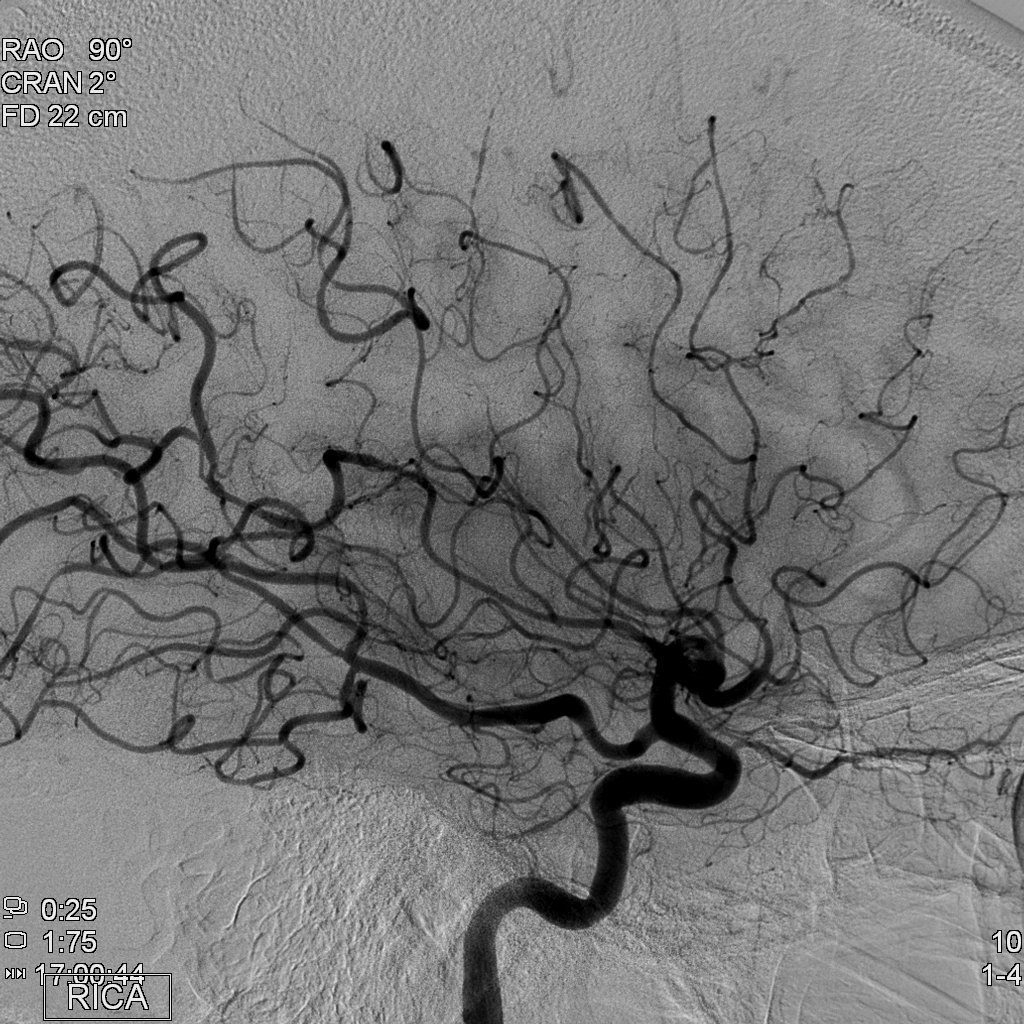

Exon-screening in Reversible Cerebral Vasoconstriction (RCVS)

Objectives: To investigate the genetic basis of RCVS using exome capture and deep sequencing.

Aim 1b: To collect the full set of phenotype information on RCVS.